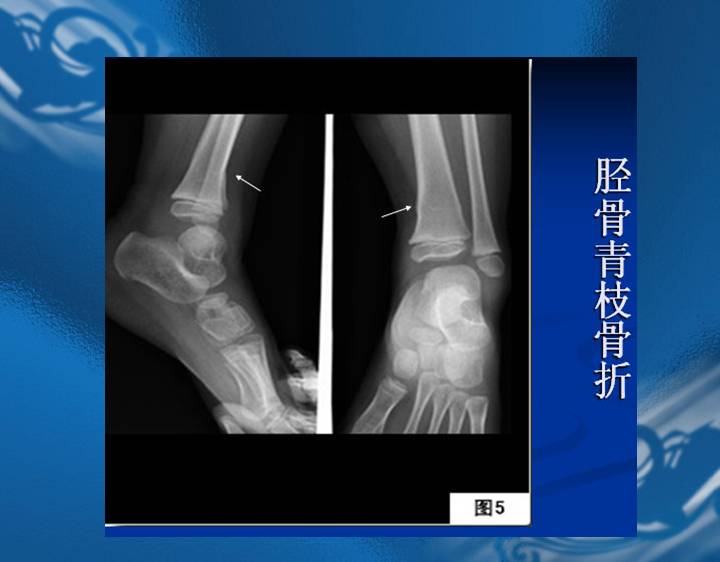

执业医师资格考试“实践技能”影像学辅导资料